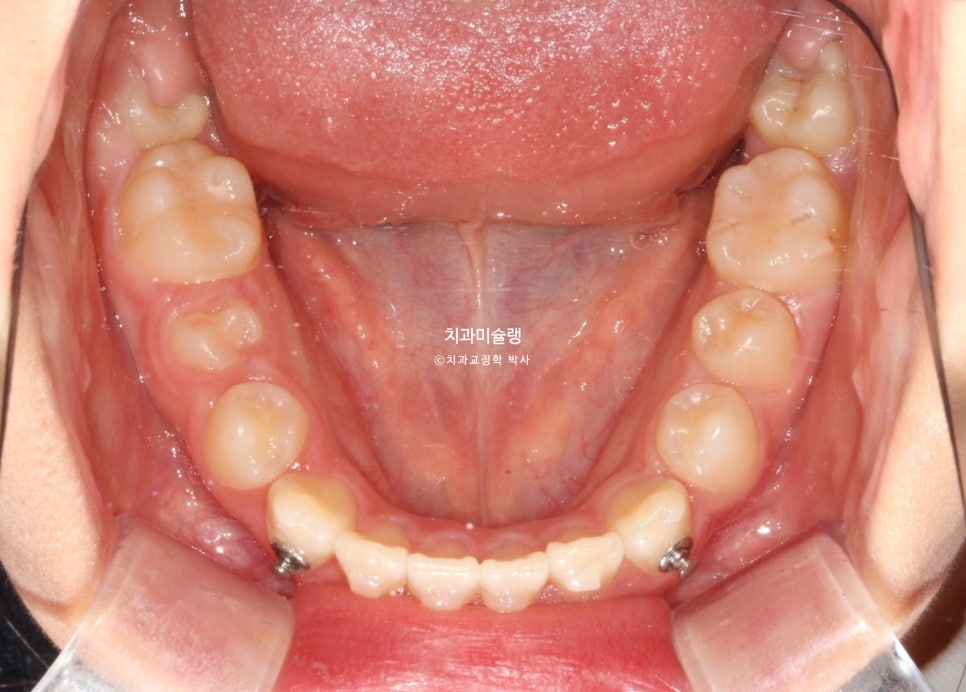

11개 장치를 다 낀 후 모습입니다.

아래 앞니가 계획만큼 뒤로 들어가지 못해서 앞니가 여전히 먼저 닿습니다.

3급 교합관계가 여전히 남아있습니다.

3급 교합관계 개선을 위해 두번째 재제작에 들어갑니다.

마지막 세트 장치 갯수는 17개이며 마찬가지로 3급 고무줄을 내내 열심히 끼도록 당부했습니다.